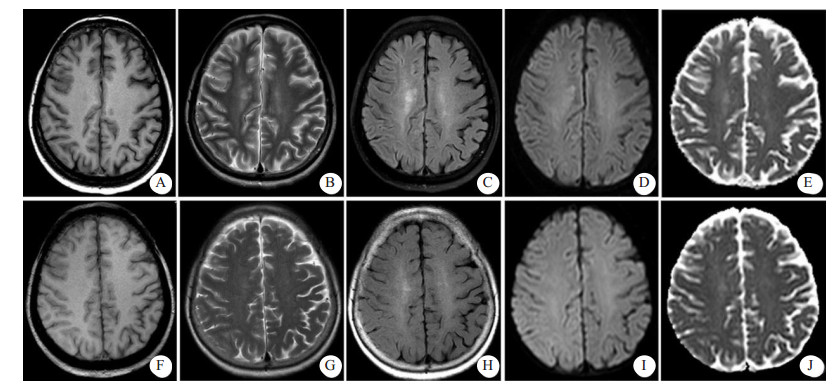

| 患者介入栓塞术后4 h(A~E),示右侧额叶部分皮质增厚,皮质T1WI信稍稍减低,T2WI、T2WI-FLAIR、DWI信号增高,ADC信号稍高;右侧放射冠区见斑片状T1WI稍低信号,T2WI、T2WI-FLAIR、DWI高信号,ADC稍高信号影。患者出现症状后第6天复查(F~J)示颅脑已基本显示正常 图 2 患者颅脑MRI检查结果 |

患者女性,71岁,2011年3月行食管癌切除术,6年来反复出现咯血症状,每次均在止血及抗感染治疗后好转。2018年1月20日患者再次出现咯血,入苏州大学附属第二医院介入科治疗。CT检查提示支气管扩张伴感染,遂于2018年1月25日在本院行支气管动脉栓塞术,分别对右支气管动脉远端、支气管动脉主干及左侧肋间动脉进行栓塞,术中使用的造影剂为碘海醇150 mL(浓度为30 g/100 mL)。术后仍出现反复痰中带血,因症状逐渐加重,患者于2018年8月13日再次来本院就诊。患者既往无高血压、糖尿病、心脏病等慢性病病史。入院后,给予患者头孢匹胺抗感染及止血、抑酸等对症支持治疗,咯血症状明显缓解。为进一步明确患者支气管动脉情况并予以处理,于8月17日穿刺右股动脉对患者施行支气管动脉造影+栓塞术,造影显示左侧两支支气管动脉与肋间动脉共干,左侧一支气管动脉血管明显增粗,紊乱,可见小片状可疑出血染色,遂对左侧两支与肋间动脉共干的支气管动脉分别予以栓塞,术中使用的造影剂为碘海醇100 mL(浓度为30 g/100 mL)。术中患者未有不适,术后患者安返病房。术后2 h, 患者无明显诱因下突然出现谵妄,查体:T 36.6℃,P 110次/min,BP 190/80 mmHg (1 mmHg=0.133 kPa),双侧瞳孔对光反射存在,左上肢肌力1级,右上肢肌力5级。急诊颅脑CT显示,右侧脑沟裂、纵裂池密度增高,局部脑实质肿胀、密度增高(图 1)。术后4 h颅脑MRI显示,右侧额叶部分皮质增厚,皮质T1WI信号稍减低,T2WI、T2WI-FLAIR、DWI信号增高,ADC信号稍高;右侧放射冠区见斑片状T1WI稍低信号,T2WI、T2WI-FLAIR、DWI高信号,ADC稍高信号影(图 2A~E);颅脑与颈部TOF-MRA显示各动脉未见明显扩张或狭窄征象。结合患者临床及影像学表现,在排除心脑血管病变后,经多学科会诊,考虑造影剂脑病。给予患者糖皮质激素抗炎、甘露醇降颅压、改善微循环及纠正电解质紊乱等对症处理,患者于术后第3天意识恢复,左侧肢体肌力明显好转。术后第6天,患者精神状态与左侧肢体肌力完全恢复,复查颅脑CT显示脑沟裂池内及局部脑实质高密度影消失,MRI各序列(图 2F~J)未见明显异常,予以出院,随访至今,患者未有不适。

临床表现轻微的造影剂脑病,影像学检查可以无异常发现。对于症状较为严重的患者,颅脑CT平扫及MRI检查常可见特征性表现。造影剂脑病的CT表现可以为脑水肿,皮质及皮质下异常高密度影,蛛网膜下腔密度增高以及局灶性高密度改变等[2, 6]。但是,有些造影剂脑病患者虽然症状严重,CT平扫也可无异常发现[4]。CT上脑实质的异常高密度影在MRI上可以表现为T2WI、DWI及FLAIR高信号灶,而ADC可无明显异常[3, 6]。这些异常的影像学表现均会在临床对症治疗后短期内消失。本例患者的CT及MRI表现与文献报道相符。